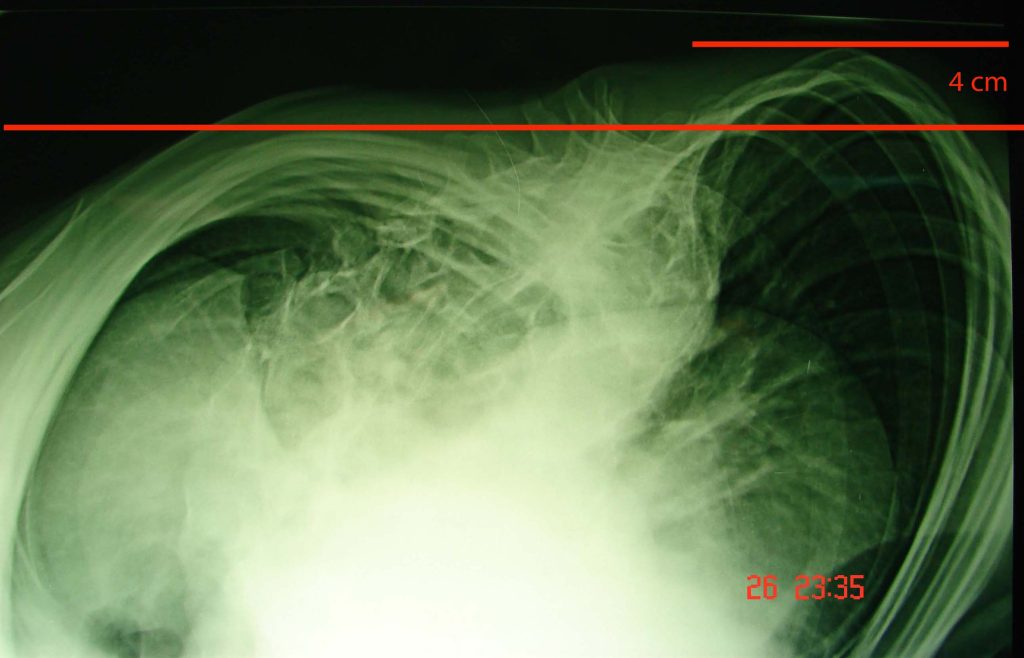

Εικόνα 5,

Προεγχειρητική ακτινογραφία του Θωρακικού τοιχώματος, η οποία αναδεικνύει τον θωρακικό ύβο. Είναι σαφής η μεγάλη ασυμμετρία η οποία υφίσταται μεταξύ του δεξιού προς το αριστερό θωρακικό τοίχωμα, συνεπεία της μεγάλης στροφής των θωρακικών σπονδύλων και της ασύμμετρης παραμόρφωσης των πλευρών.